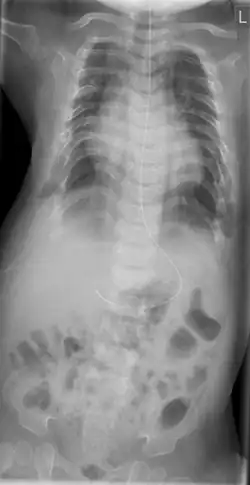

Die Asphyxierende Thoraxdysplasie ist eine sehr seltene angeborene Skelettdysplasie aus der Gruppe der Kurzripp-Polydaktylie-Syndrome mit sehr kurzen Rippen und entsprechend schmalem Thorax, kurzen Gliedmaßen und typischen Veränderungen im Röntgenbild. Sie zählt zu den Ziliopathien und verläuft häufig letal.[1][2][3] Die Erkrankung kann als Subtyp des Joubert-Syndromes (Joubert-Syndrom und verwandte Krankheiten) angesehen werden.[4]

Der Ausprägungsgrad der Veränderungen kann beträchtlich unterschiedlich sein. Klinische Kriterien sind:[1][2] Thoraxdeformität mit langem, schmalen Thorax mit Atemnot des Neugeborenen infolge Platzmangels für die Lunge; Kurze Extremitäten mit Kleinwuchs, eventuell Polydaktylie; Im späteren Kindesalter können Niereninsuffizienz, Retinopathie, Fibrosierung von Leber und Pankreas auftreten.

Die klinische Verdachtsdiagnose wird im Röntgenbild gesichert. Diagnostische Kriterien sind:[1][2][14]

- Kurze, horizontal verlaufende Rippen

- Schmale Beckenschaufeln mit dreizackartiger Begrenzung des Unterrandes, Pfannendach horizontal verlaufend und spornartig nach kaudal weisend

- Vorzeitige Verknöcherung der Femurepiphyse

- Distal betont verkürzte Röhrenknochen

- Zapfenepiphysen der Mittelphalangen